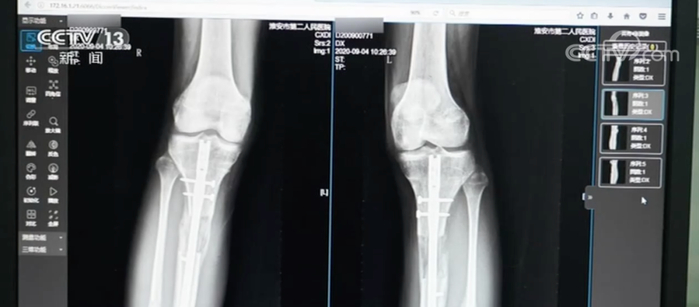

据淮安市第二人民医院骨科主治医师王磊介绍,这名男性患者22岁,当时是拄双拐来就诊的。通过拍X片发现,男子双小腿做了增高手术,骨折断端没有完全愈合好,手术部位的皮肤有炎症反应。

患者自述今年5月在韩国做的“断骨增高手术”,手术时,父母并不知情,目前仍不能独立行走。医生建议患者口服促进骨折愈合的药物,适当增加负重锻炼。如果三个月内仍然没有骨愈合迹象,应该考虑施行自体骨移植手术治疗。